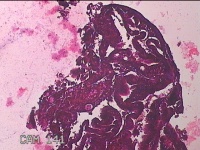

宫腔内容物

性别

女

年龄

46岁

临床诊断

子宫异常出血 子宫内膜息肉?高泌乳素血症待查 慢性宫颈炎

一般病史

阴道流血不规则22天。

标本名称

大体所见

灰白暗红色不规则碎组织3.3x2.8x0.7cm一堆。